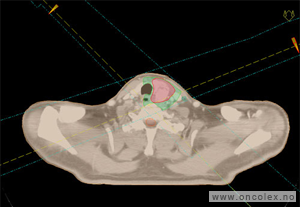

Eksempel på CT-bilder til doseplan

Hovedsvulst er markert med grønt, lymfeknuter med turkis, og risikoorganer er markert med oransje.